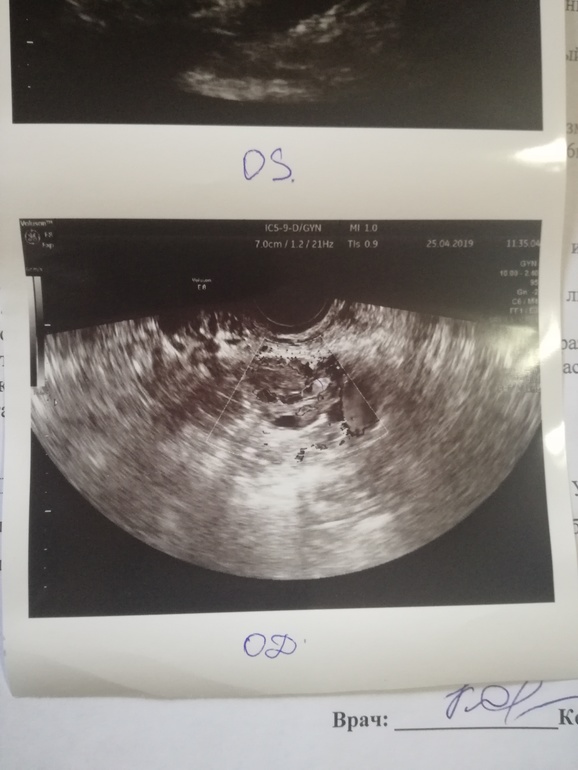

УЗИ, всё плохо?

Девочки, пожалуйста , скажите что здесь насмотрели у меня . Глаза на мокром месте, одна труба левая , правая удалена